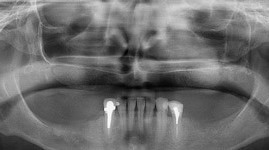

- Cas 2: vues panoramiques

PENDANT REHABILITATION 3 SECTEURS MOLAIRES